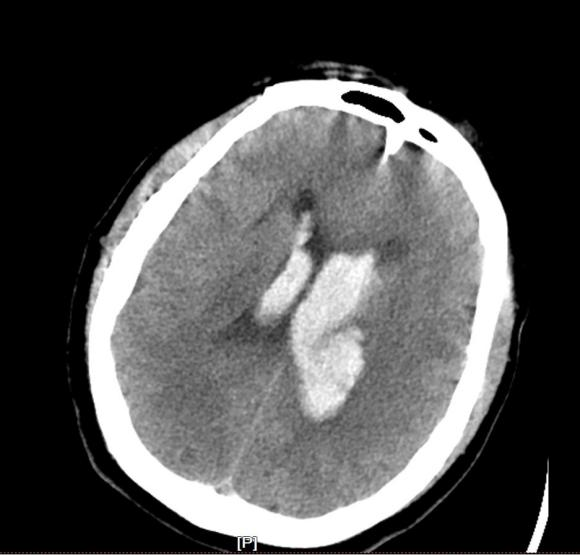

神经外科陈楠主任医师迅速到位,全面评估后明确手术指征。在多科室紧密配合下,于12月9日凌晨为患者实施急诊“双侧脑室钻孔引流术”。手术过程顺利,术后患者转入ICU监护治疗。

在神经外科团队的持续跟进与精细化管理下,患者目前神志已转清,恢复良好。该病例的成功救治,标志着我院在危急重症神经外科急诊手术能力上实现新突破。

图3

(配图说明:图1-2为术前颅脑CT,显示脑室系统血肿铸型;图3为术后复查CT,显示引流管位置良好;图4为手术团队术中操作场景。)